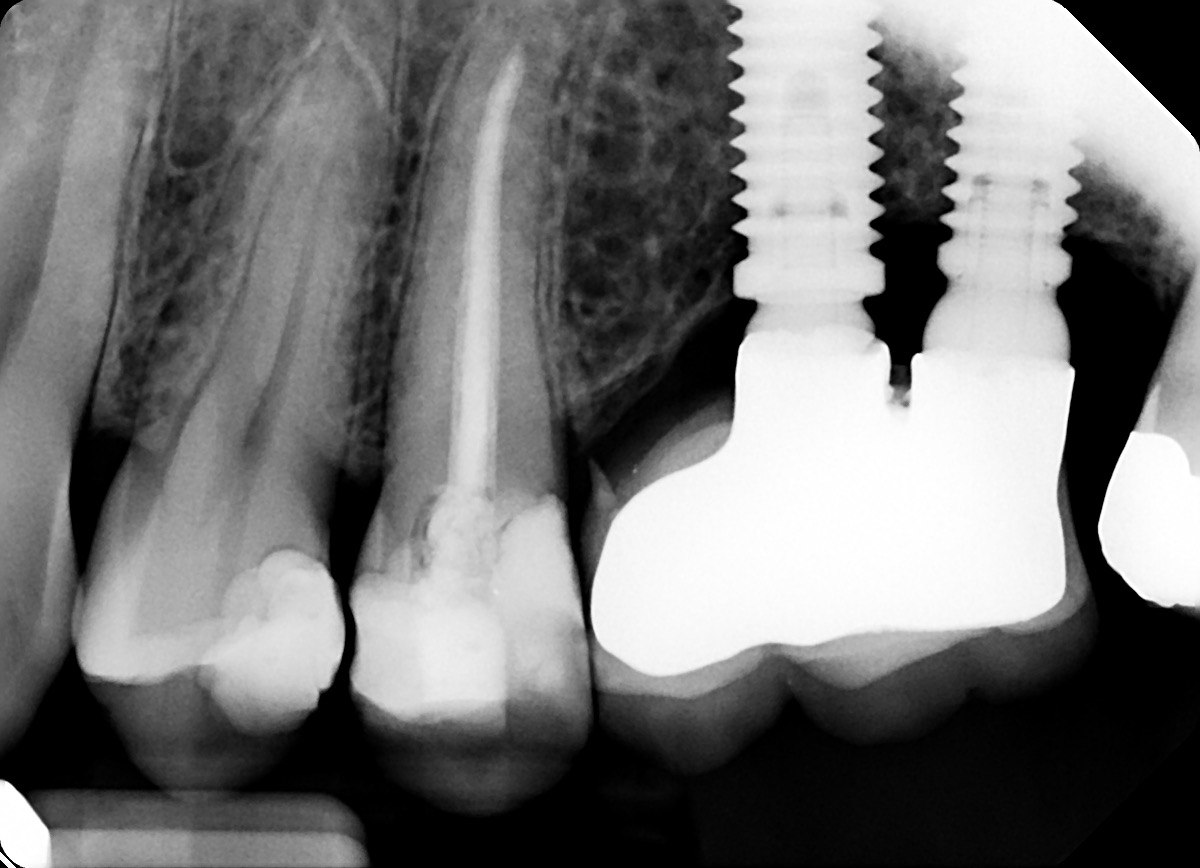

1. What is the condition in the distal surface of the tooth # 4.6?

2. What is the condition in the distal surface of the tooth # 4.7?

3. What condition can be detected in mesial surface of the tooth # 2.5?

4. What is the condition in the distal surface of the tooth # 3.4?

5. What is the condition in the distal surface of the tooth # 3.3?

6. What is the condition on dista surface of the tooth # 3.7?

7. What condition can be seen in the tooth # 4.4?